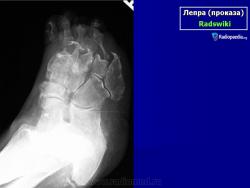

Что касается нервной формы проказы (рис. 216), то наиболее ранним, постоянным и общим рентгенологическим ее проявлением служит остеопороз. IK остеопорозу рано присоединяются явления остеолиза. Иконография (т. е. описание картины) остеолиза дается различными авторами в традиционном для лепрологии стиле в чрезвычайно тонких и кропотливых внешне описательных образах. Здесь преобладают сравнения с общеизвестными предметами, как, например, отточенными кончиками карандаша, шахматными пешками и другими фигурами, кнопками, пуговицами для воротника, запонками, тающими свечами, обсосанными леденцами, столбиками, иглами и т. д. Существенно то, что налицо частичное или полное рассасывание и исчезновение костных элементов без их замещения другой тканью и без продуктивной репаративной реакции. Характерно истончение и укорочение костей, в первую очередь ногтевых фаланг. Рассасывание ногтевой фаланги начинается с ее ногтевого отростка. Структура бугорка становится крупнопористой, ноздреватой. Затем срезается дистальный или боковой край, развивается плоская или вогнутая узура, постепенно увеличивающаяся, а затем и весь ногтевой отросток сходит на нет; обнажается шейка. Основание фаланги рассасывается с одного края или с обеих сторон, иногда и целиком. В дальнейшем без каких-нибудь клинических признаков очередь доходит до фаланг средних и основных, а также пястных и плюсневых костей, с переходом на запястье и предплюсну, порой до полного исчезновения скелета одного, нескольких, многих или всех пальцев.